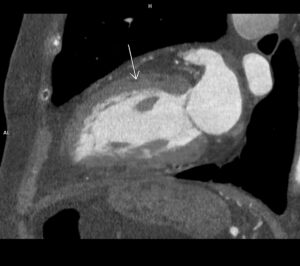

Figura 1: reconstrucţie oblic coronală aortă preoperator

Discuţie caz nr 104: Pacient în vârstă de 51 de ani este descoperit cu multiple dilatații anevrismale de tip sacular la nivelul aortei toracice și abominale precum și la nivelul arterei subclavii stângi și la nivelul arterelor renale; în plus, anevrismul de aorta abdominală infrarenal e parțial trombozat cu diametrul de 8 cm. Este operat atât supra cât și subdiafragmatic, cu menținerea dilatației anevrismale a arterei subclavii stângi și a unor creșteri de calibru a aortei la nivelul crosei și la limita dintre aorta toracică și cea abdominală.